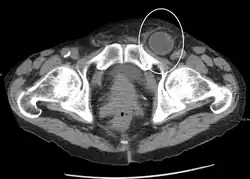

Hérnia inguinal encarcerada, como visto na TC

No diagnóstico de hérnias abdominais, a imagem é o principal meio de detectar hérnias diafragmáticas internas e outras hérnias não palpáveis ou não suspeitas. A tomografia computadorizada com múltiplos detectores (TCMD) pode mostrar com precisão o local anatômico do saco de hérnia, o conteúdo do saco e quaisquer complicações. A TCMD também oferece detalhes claros da parede abdominal, permitindo que as hérnias sejam identificadas com precisão.[9]